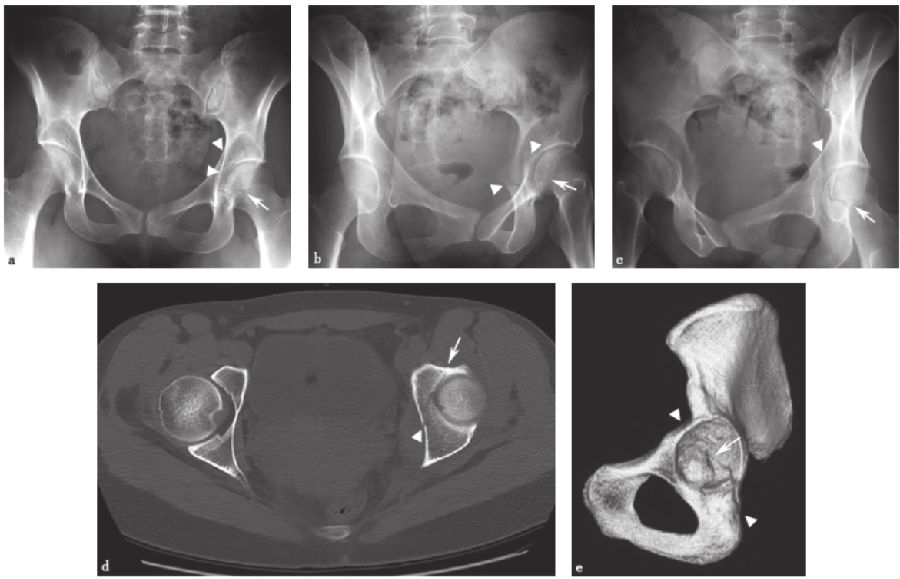

2、T形髋臼骨折:

T形髋臼骨折(图11)是一种横向髋臼骨折并向下延伸至闭孔环的组合。它类似于双柱断裂,因为它破坏了闭孔环;另一种相似性是髂耻线和髂坐线的破坏。然而,骨折并不涉及髂骨翼,这有别于双柱骨折。

图11 T形髋臼骨折a.骨盆正位X线片;b、c.双侧斜位骨盆X线片;d.轴向CT扫描;e.髋臼侧面三维CT扫描,右侧半骨盆和股骨去除。图中箭头示闭孔环骨折,直线箭头示通过髋臼的横行分量。注意CT扫描时横向髋臼骨折成分的特征性斜向矢状取向,X线片上横向相对于髋臼。

横行骨折线实际上并不在解剖学的横行平面内,而是横行于髋臼。由于髋臼的杯形通常向下和向前倾斜,所以横向断裂面呈现类似的取向。因此,在X线片上,破坏髂耻骨和髂骨线的骨折线在髋臼斜平面的上方和内侧走行。通过观察髋臼面,这是最好的评价。在CT上,这种横向骨折成分被看作是从髋臼内侧和上方走行的矢状骨折。